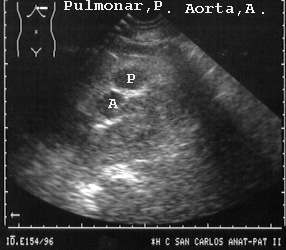

Cuando la arteria pulmonar esta vacía es difícil de ver pero si está llena es visible con facilidad y al punzar el interior demostramos la naturaleza de lo que hay dentro que en este caso era sangre (Fig 25).

25AORTPU.JPG (29010 bytes)

Fig 25